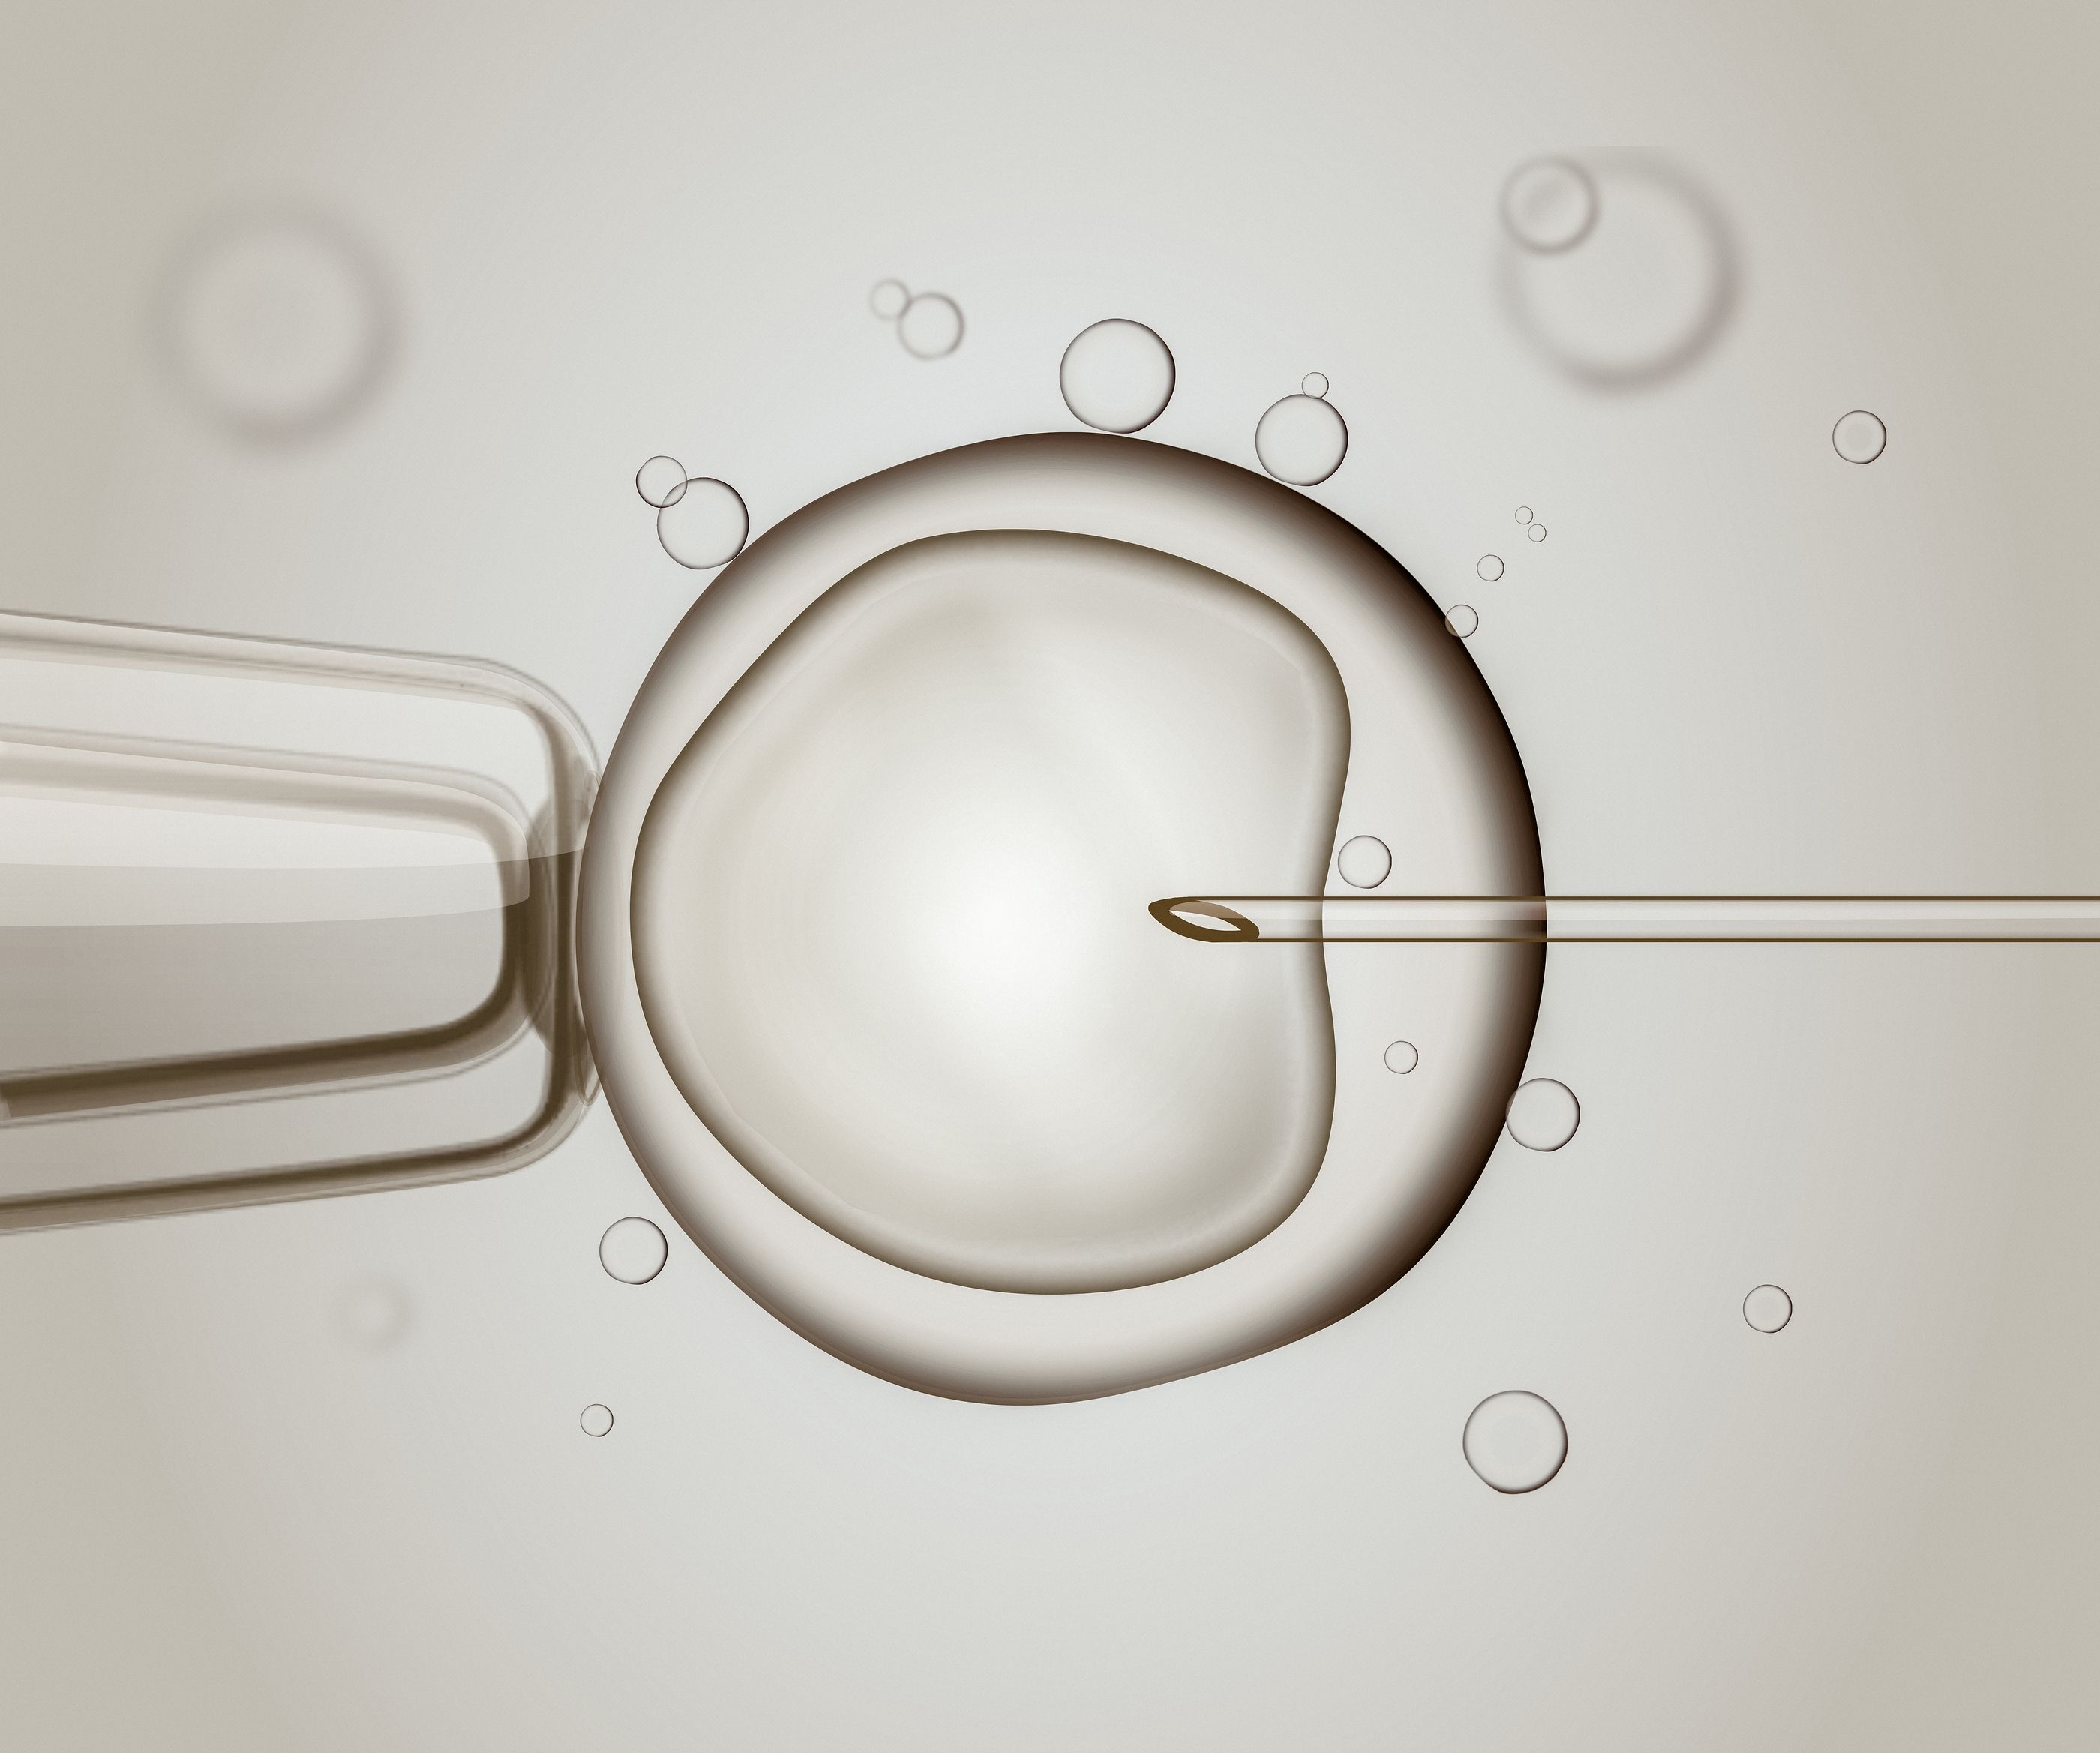

We offer a full spectrum of female and male fertility care, including IVF, egg freezing, genetic screening (PGD/PGS), egg donation, surrogacy and LGBTQ+ fertility. Build your beautiful family with Aspire Fertility.